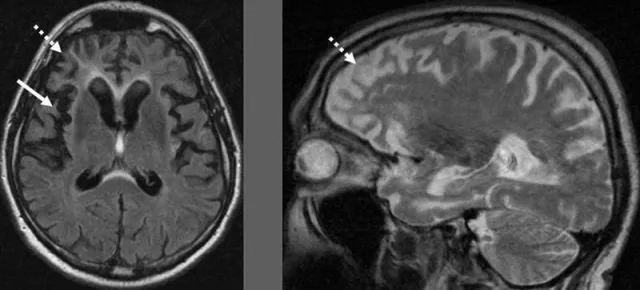

Obwohl die genauen Ursachen, die zu einer primären Demenzerkrankung wie Alzheimer führen, bislang noch unklar sind, scheinen Faktoren wie Rauchen, eine genetische Veranlagung, Bluthochdruck oder Ablagerungen im Gehirn und den Blutgefäßen die Erkrankung zu begünstigen. "Daneben können aber auch andere Grunderkrankungen zu einer sogenannten sekundären Demenz führen", ergänzt Dr. Ursula Jonas, Apothekerin bei der Online-Apotheke und Versandapotheke mediherz.de.